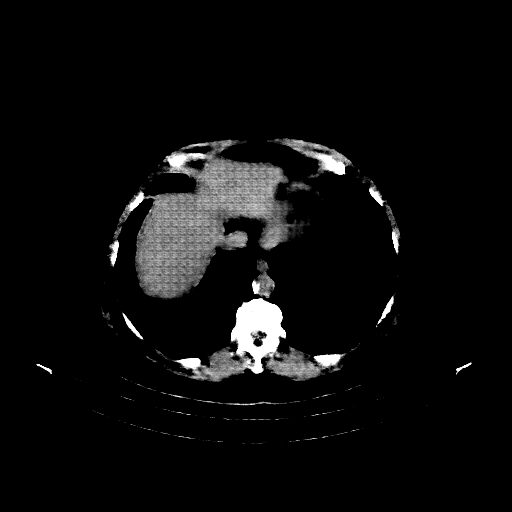

Generated VENOUS CT scan (A→B translation)

Full window (WL 1023.5, WW 4095 β†’ Low βˆ’1024, High +3071)

Actual HU range: [-876.3, 832.7]